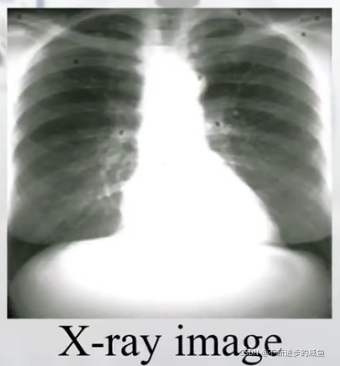

(6)X光(X-ray):

(3)X-ray图像:很好描述肺结构